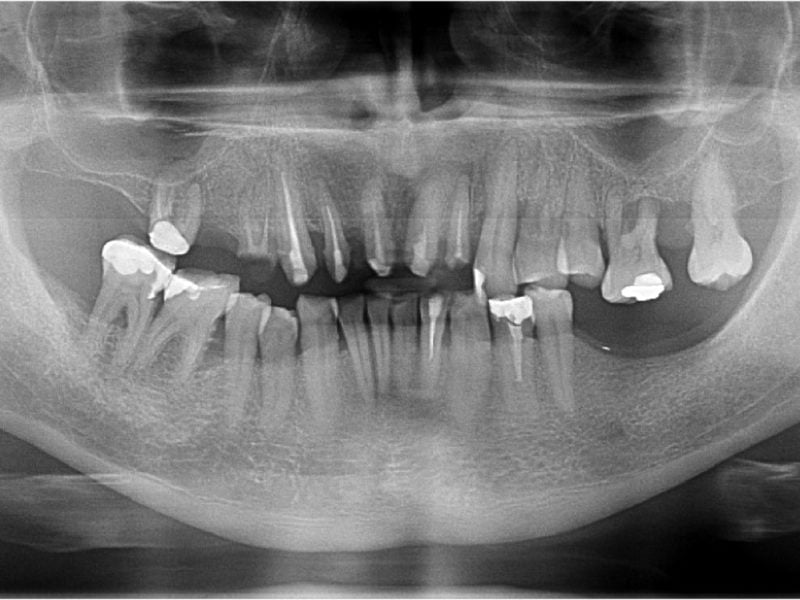

Aesthetic-functional Restoration In Frontal Post Extractive Site

Dr. ALESSANDRO CECCHERINI Country: Italy Gallery Patient’s Data: Age: 45 Sex: Female Smoker: No Pathologies: None Hygenic state: Fair Alergies: None The treatment plan created for this patient consists in the insertion of an EV implant in the anterior area. Given the extremely aesthetic position of the site, for an optimal aesthetic result the volumes […]